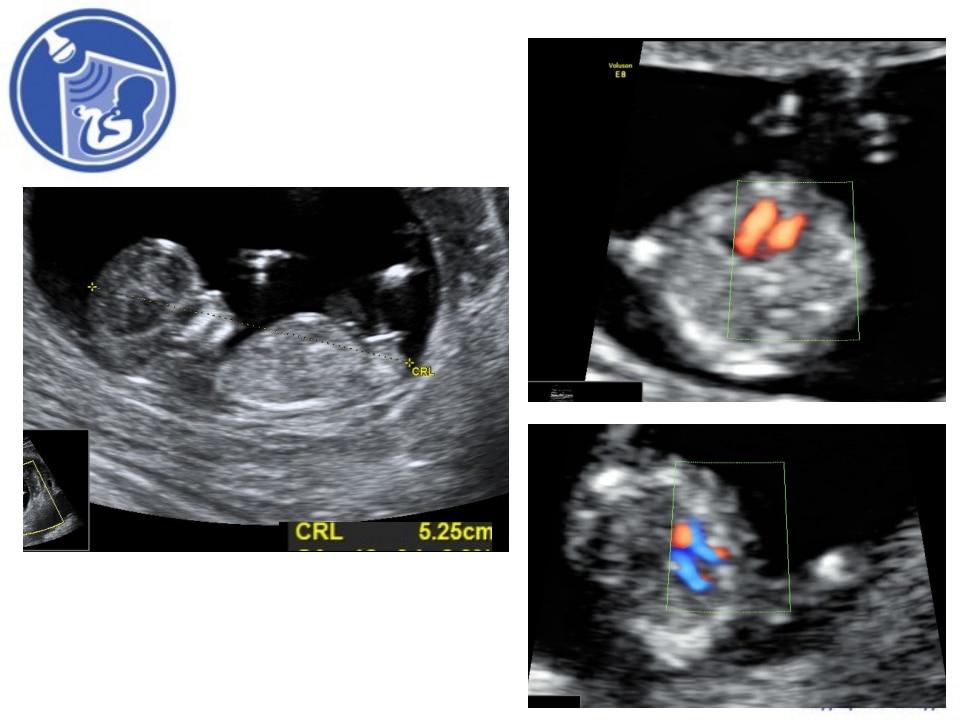

Вопрос 1

Пациентка пришла на УЗИ в 12 недель 3 дня.

- КТР 60 мм;

- ДТВП 1.9 мм, носовая кость визуализируется;

- кровоток в венозном протоке и трикуспидальном клапане нормальный.

Какой диагноз можно поставить по данным клипам сердца, каков риск ХА, какая тактика дальнейших действий?